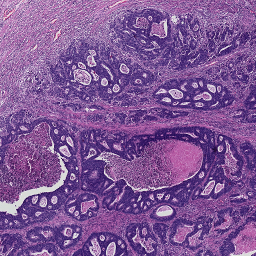

A set of 74 histological slides from 74 patients was prepared from surgically excised rectal carcinomas in patients who had not received neoadjuvant chemotherapy and/or radiotherapy. Slide preparation involved standard fixation of 2m tissue sections and H&E staining. Whole-slide scanning was performed at 200X magnification (pixel resolution = 0.455 m) using a Hamamatsu NanoZoomer 2.0-HT C9600-13 scanner (Herrsching, Germany), which produce 74 gigapixel whole-slide images. Manual annotations of 9 tissue classes were made by an expert using the open source software ASAP555github.com/GeertLitjens/ASAP developed in-house, which included: (i) tumor, (ii) stroma, (iii) necrosis, (iv) muscle, (v) healthy epithelium, (vi) fatty tissue, (vii) lymphocytes, (viii) mucus and (ix) blood cells (see Figure 2). All annotations were successively thoroughly checked by a pathologist and corrections were made when necessary. In the rest of the paper, we refer to this dataset as rectal cancer (RC) data.

A dataset of colorectal cancer images and patches from 10 patients was recently made publicly available [4]. The test dataset consists of two subsets. The first subset contains 5000 patches of 150150 pixel extracted from 10 H&E slides of CRC cases. The patches contain 625 examples of 8 tissue types, namely (i) tumor epithelium, (ii) simple stroma, (iii) complex stroma, (iv) immune cell conglomerates, (v) debris and mucus, (vi) mucosal glands, (vii) adipose tissue, (viii) background. We name this subset as CRCp. The second subset contains 10 tiles of size 50005000 pixel of H&E stained CRC tissue samples, which we call CRCt.

3.2 The importance of stain normalization

The definition of classes in our RC data is slightly different from the one coming with the CRC dataset. Therefore, we grouped corresponding classes as described in Table 2, which resulted in a 6-class problem, used to evaluate the performance of the trained ConvNet applied to CRC data. Applying the ConvNet directly to CRC data gave a poor accuracy value of 50.96% (experiment A). Based on this result, we investigated the role of staining in this classification task. For this purpose, we selected a representative RC image from the RC cohort as the template image to define the mapping parameters for the SN1 and SN2 algorithms999The function for SN1 is available in the form of look-up table at https://github.com/francescociompi/stain-normalization-isbi-2017. Successively, we stain-normalized patches in the CRC dataset and classified it again with the same ConvNet. Stain normalization allowed to remarkably improve the accuracy by more than 20%, reaching values of 75.55% (experiment B) and 73.99% accuracy for SN1 and SN2 respectively. Besides the difference in accuracy, we found that SN2 failed to normalize 3 patches of adipose tissue, and it tends to force color normalization regardless of the type of tissue considered. As an example, in Figure 4, two CRC patches are depicted, containing tumor and blood cells respectively. While both SN1 and SN2 correctly normalize stain for the tumor patch, the characteristic red color of blood cells is completely lost using SN2, while SN1 keeps a substantial component of the red channel.